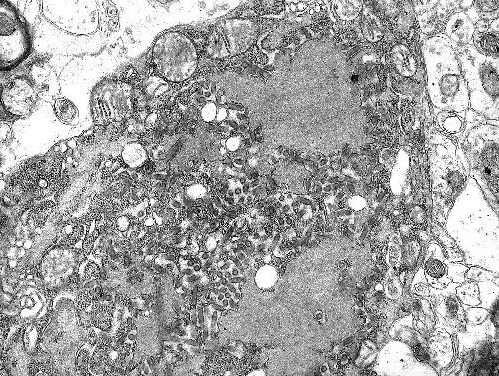

马尔堡病毒的病毒粒子

上面的图像是通过透射电子显微镜观察到的若干马尔堡病毒的病毒粒。埃博拉病毒和马尔堡病毒都属于同一家族的病毒,称为纤维病毒家族。